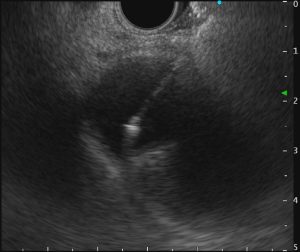

肝門部胆管癌に対するEUS下胆道ドレナージ